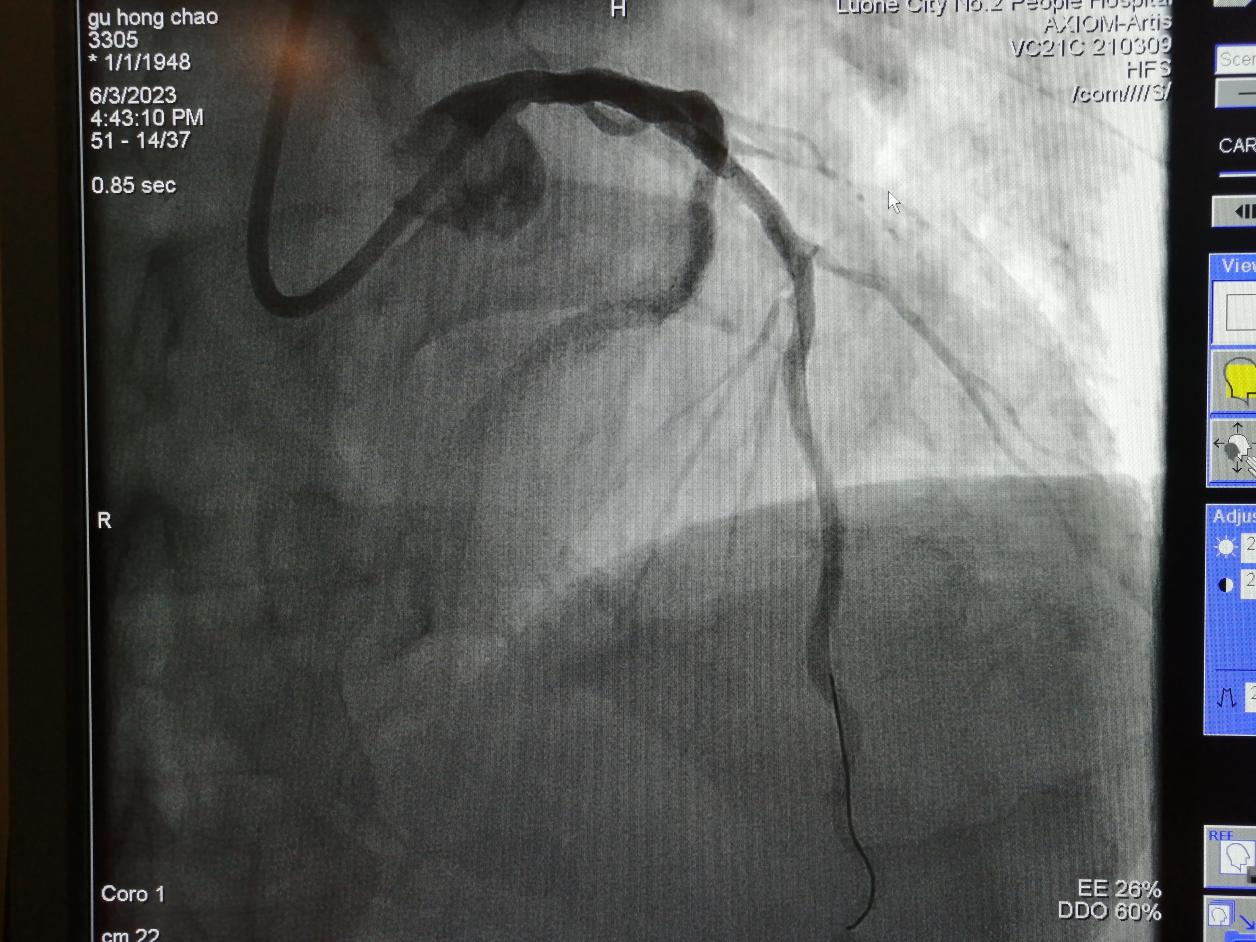

術(shù)前:

75歲的谷大爺,4年前行冠脈介入手術(shù)。近日,因“胸痛5天”入住心血管內(nèi)科,經(jīng)檢查冠脈造影發(fā)現(xiàn),前降支長(zhǎng)段狹窄合并鈣化。

金叔宣教授帶領(lǐng)心血管內(nèi)科介入團(tuán)隊(duì)為谷大爺制定了個(gè)體化的手術(shù)治療方案,即行血管內(nèi)超聲,旋磨前降支,后置入心臟支架1枚。